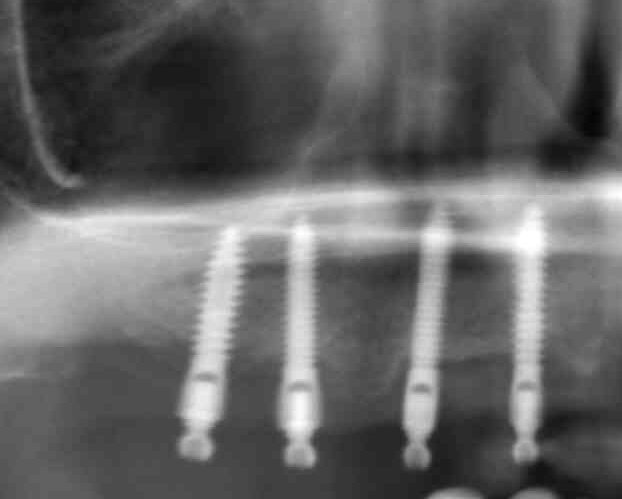

Buenas compañers! ¿Podríais ayudarme a identificar estos implantes colocados en arcada inferior en Idental, abril de 2018? Muchas gracias!!!